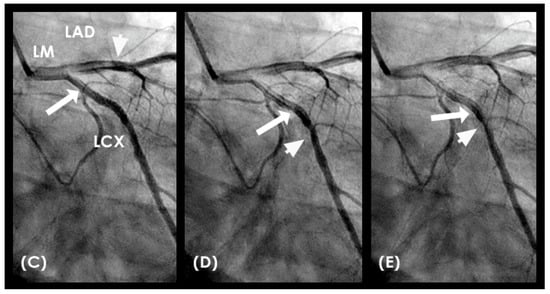

The secondary objective was to examine the relationship between antinodes and the presence of coronary stenoses, as well as between nodes and minimally diseased or lesion-free coronary segments. Ultimately, the investigation aimed to establish antinodes as potential markers for high-pressure surges linked to intimal damage. These locations of antinodes are used to construct a coronary acoustic activity (or action) map, enabling the identification of existing lesions, forecasting the progression of current lesions, and predicting the development of potential future lesions. Table 5 outlines the protocol on how to identify and label the five zones of compression and rarefaction (antinodes) and the minimal or lesion-free segments (nodes) within the coronary arteries. The protocol to identify the antinodes of compression and rarefaction and the nodes in between the antinodes uses the novel coronary dynamic angiographic technique. The protocol is listed in Table 5 and Figure 16A–E.

FIRST Compression Zone with High Contrast Concentration. Angiographic Identification. During diastole, coronary blood flow reaches a relatively high velocity. At the onset of systole, the contraction of the left ventricle abruptly interrupts this flow, triggering a water hammer effect. This results in the formation of a retrograde pressure wave, which collides with the antegrade flow at a critical timing when diastole transitions into systole. The initial reflection point, designated as location 1, is characterized by pockets of prolonged concentration of contrast agent, seen as a disorganized mixing of dark (contrast) and light (blood) materials (blue arrow in Figure 16E). These black-and-white pockets may signify turbulent flow, mirroring the surge of pressure in the local area (Figure 16A–D).

CRITICAL THINKING. High Concentration of Contrast at location 1 as a Marker of Compression Activity. During a typical cardiac cycle, antegrade blood flow accelerates during diastole and transitions rapidly into the systole, initiating a water hammer phenomenon that generates a retrograde pressure wave. This retrograde wave propagates at nearly the speed of sound and undergoes multiple reflections within one or two diastole–systole cycles along the length of a coronary artery. These reflections produce hundreds of retrograde pressure waves, which may synchronize with antegrade waves to form resonant patterns or, conversely, cancel out. The wave reflections occur at distinct locations: the diastole-to-systole junction (location 1), the coronary artery ostium (location 4), and the systole-to-diastole junction (location 2). The resulting wave dynamics display features of acoustic resonance, with regions of high contrast concentration corresponding to antinodes—pressure peaks associated with arterial damage or the progression of atherosclerosis (Figure 16E). High-contrast regions at locations 1 and 4, observed in coronary angiography, likely represent zones of compression and rarefaction, indicative of pressure surges that may compromise the intimal layer. The critical challenge lies in determining how these observations and hypotheses can be rigorously validated.